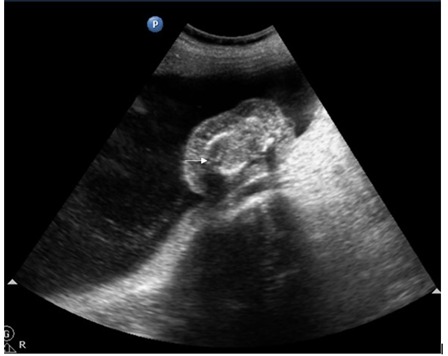

In the TRAP sequence associated with twins, the normal twin ‘pumps’ blood to the abnormal twin, called the ‘recipient’ twin, through abnormal artery-to-artery and venous-to-venous communications in the placenta. This is in conjunction with the vascular anastomosis, which takes place in TRAP syndrome.4 (Figure 2 - Figure 7).

Figure 2,3 Trans-abdominal USG shows an abnormal fetus with grossly formed lower torso and lower limbs without any discernible visceral organs and an echogenic structure casting a distal acoustic shadow, probably representing the spine of the abnormal fetus (white arrow).